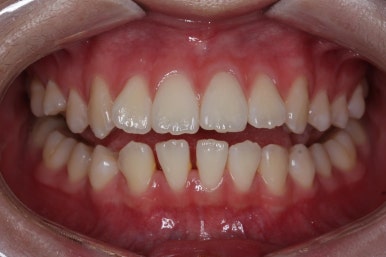

전후사진 비교입니다.

좌측 사진들이 부산교정 키다리아저씨치과에서 치료를 하기 전 모습이고 우측 사진들이 결손치아 교정을 마친 후의 모습입니다.

마찬가지로 좌측이 치료 전, 우측이 치료 후의 모습입니다.